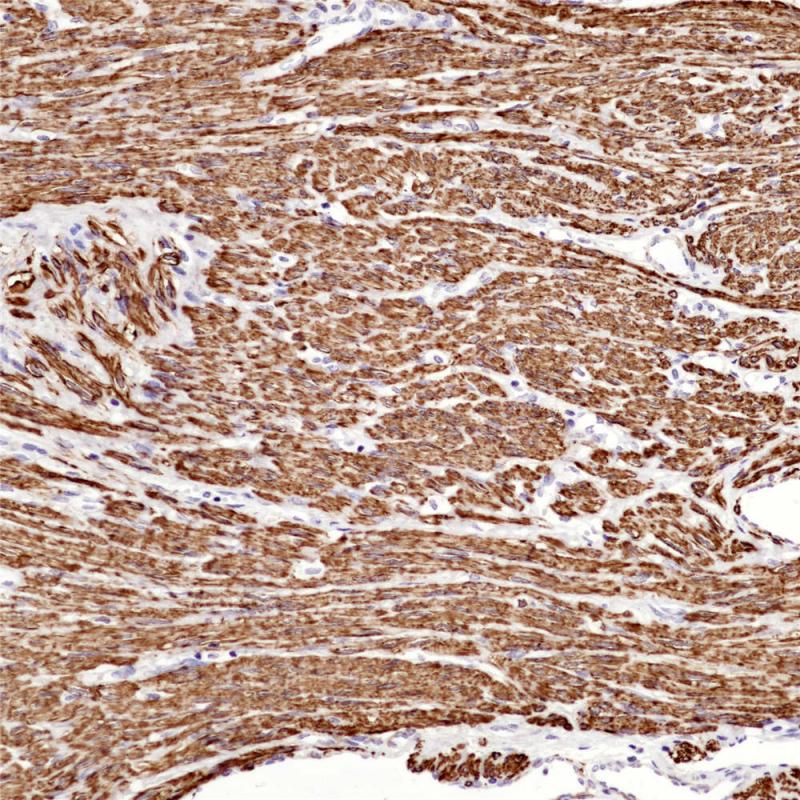

平滑肌肌球蛋白重链是平滑肌细胞浆内的结构蛋白,与平滑肌收缩功能相关。在平滑肌早期发育阶段即有表达,常用于间叶肿瘤的诊断和分类。也可用于乳腺肌上皮细胞的检测,有助于鉴别乳腺原位癌与浸润癌。

阳性对照

子宫肌瘤